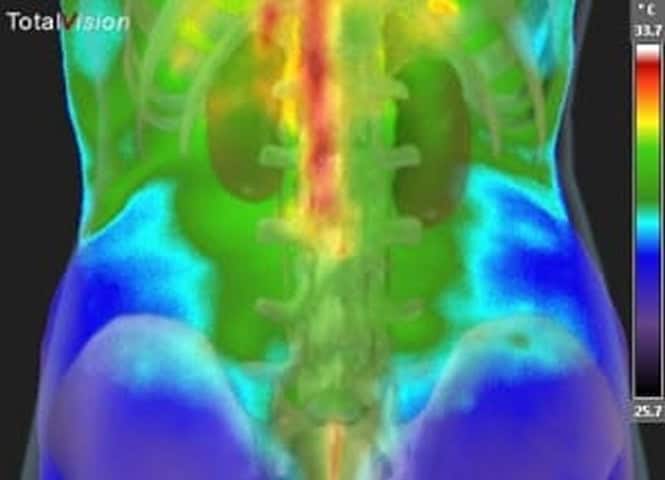

Medical thermal imaging is a sophisticated assessment method that creates detailed heat maps of your body using advanced infrared technology.

This innovative approach works by identifying and visualizing temperature differentials and patterns on your skin’s surface, offering unique insights into your body’s functioning.

Every cell in your body emits heat, creating distinct thermal patterns that our advanced imaging system can identify.

These patterns, displayed as detailed digital images, reveal temperature differentials that may indicate areas that require attention. Using our highly sensitive infrared camera system and patented software, we capture these thermal patterns and transform them into precise visual maps where different colors represent varying temperature levels.

The process works on a fascinating principle: your body’s natural infrared emissions create a unique thermal signature.

Behind the images is science. Our sophisticated imaging system detects these emissions and converts them into detailed digital images. Areas with increased blood flow or metabolic activity typically appear as warmer regions, while areas with reduced activity appear cooler. These variations can provide valuable information about your body’s current state.